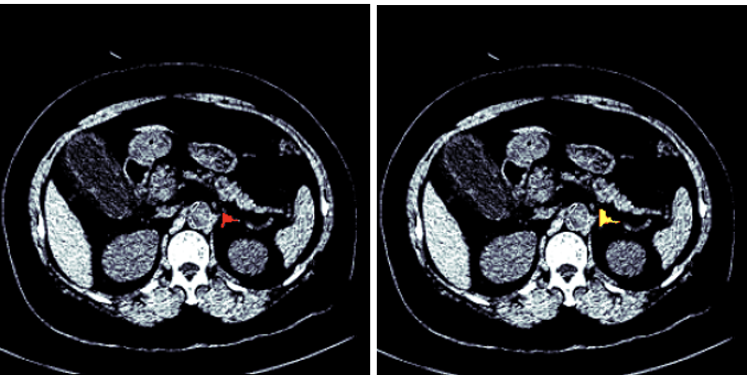

Figures 1 and 2 show the segmented model output for both right and left adrenal gland from a CT scan image from the AMOS dataset.

Figure 2: Segmentation of a left adrenal gland (AMOS dataset)